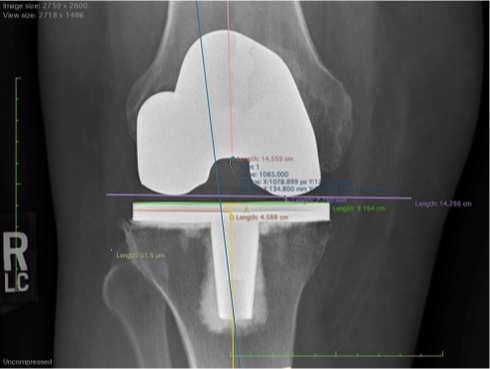

Total Knee Arthroplasty